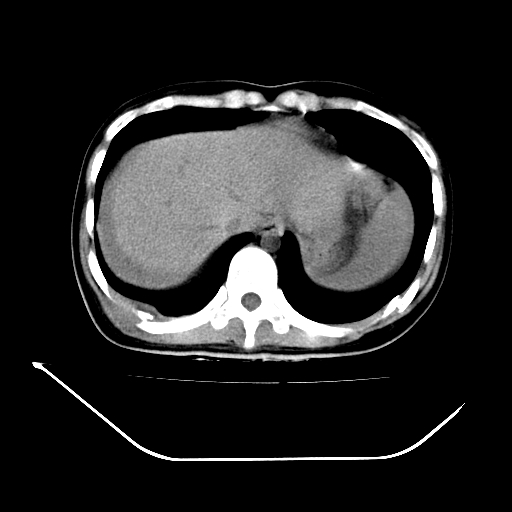

以下是引用liuyue在2008-7-19 13:02:00的发言:[br]1.肝右叶后下段及右肾挫裂伤伴腹腔积血。[br]2.右侧多发性肋骨骨折、横突骨折、右髂骨骨折伴周围软组织挫伤。[br]3.右侧腰大肌肿胀,并可见低密度影,如为气体,则肠道挫裂伤待除外。

以下是引用zhengfaming在2008-7-19 14:42:00的发言:[br]1.肝右叶后下段及右肾挫裂伤伴腹腔积血。脾脏挫裂伤待排[br]2.右侧多发性肋骨骨折、横突骨折、右髂骨骨折伴周围软组织挫伤。[br]3.右侧腰大肌肿胀,并可见低密度影,如为气体,则肠道挫裂伤待除外

以下是引用道哥在2008-7-19 16:52:00的发言:[br]肝右叶后下段及右肾挫裂伤、脾破裂伴腹腔积血。[br]2.双侧多发性肋骨骨折、横突骨折、右髂骨骨折伴周围软组织挫伤。[br]3.右侧腰大肌肿胀,并可见低密度影,如为气体,则肠道挫裂伤待除外。